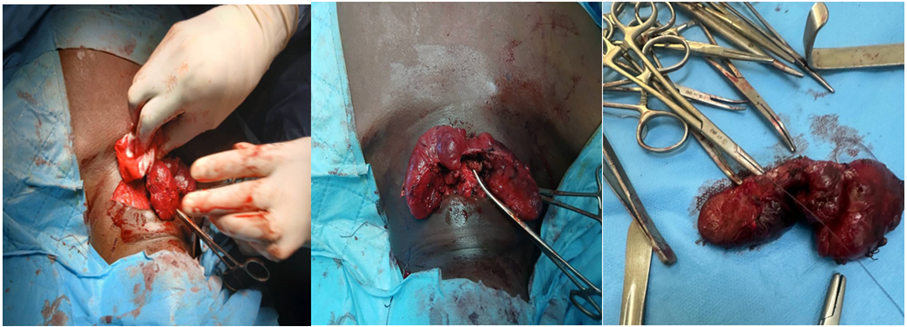

Treatment consisted of cessation of all physical activity and bed rest at home, propranolol 40 mg morning and evening after meals, and carbimazole 40 mg in the morning after breakfast. Blood count and transaminase levels were monitored every 10 to 15 days for the first 2 months of treatment. The outcome was favorable after 2 months of treatment, marked by an absence of complaints, a slight regression of bilateral exophthalmos, and a normalization of heart rate. On the paraclinical level, TSHus at 0.000 mIU/l, FT4 at 12.55 pmol/l, hemoglobin level at 12.8 g/l, white blood cells at 4900/mm3 with neutrophil polynuclear cells at 1860/mm3, normal transaminases (ALAT : 36 IU/l, ASAT : 39 IU/l). Carbimazole was reduced to 20 mg per day (maintenance treatment) and propranolol was stopped. A thyroid hormone assessment was performed a month later, still demonstrating euthyroidism. The patient underwent a total thyroidectomy (Figure 3) with thyroid and nodular biopsy; and the patient was supplemented with Levothyroxine 12.5 micrograms per day.

Figure 3: Enlarged thyroid of patient with isthmic nodules.